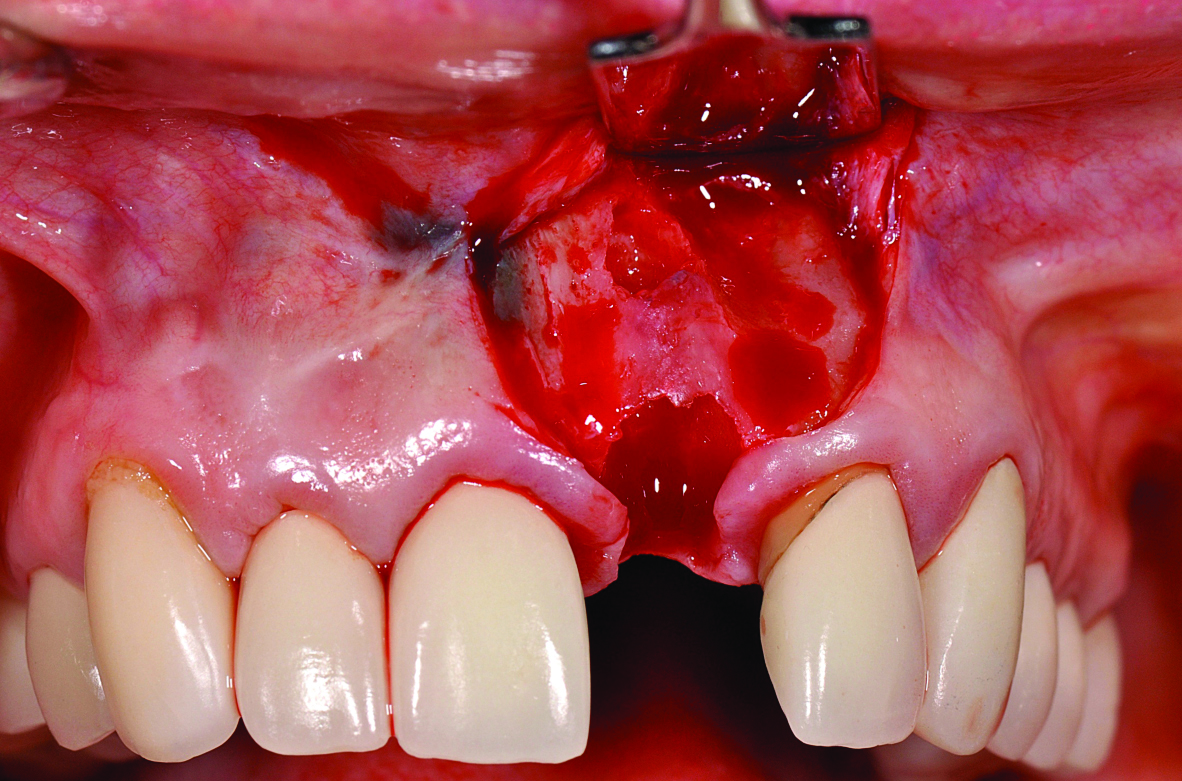

Similarly, the approach of immediate implant placement and restoration is increasingly being used by clinicians, although the esthetic risks are considered high by some, because the procedure requires precision and careful management of hard and soft tissues. Aside from the patient-driven rationale for this approach, in appropriately selected cases, tissue guidance by the fixed restoration may lead to enhanced papilla development and better post-restoration facial tissue stability, because the soft tissues are less likely to slump or lose their anatomy. De Rouck and coauthors reported enhanced results with immediate versus delayed implant restoration.21 The case illustrated in Figure 17 involved extraction of tooth No. 9 and immediate implant placement, placement of a xenograft material in the residual horizontal defect, and fabrication/delivery of a provisional restoration. Implant placement at the time of tooth extraction may not prevent ridge resorption from occurring, but management of the residual horizontal defect between the socket wall and implant surface can influence the tissue level, particularly on the facial aspect.22 It is the authors’ observation that specific treatment with an anorganic bone graft (xenograft) can reduce buccal ridge resorption, and as a consequence, will positively influence the facial soft-tissue levels.

Fig 17. Preoperative view of the fractured No. 9.

Figure 17

Fig 18. After immediate implant placement and provisionalization, the removal of the temporary crown reveals a healthy and shaped gingival sulcus of favorable volume.

Figure 18